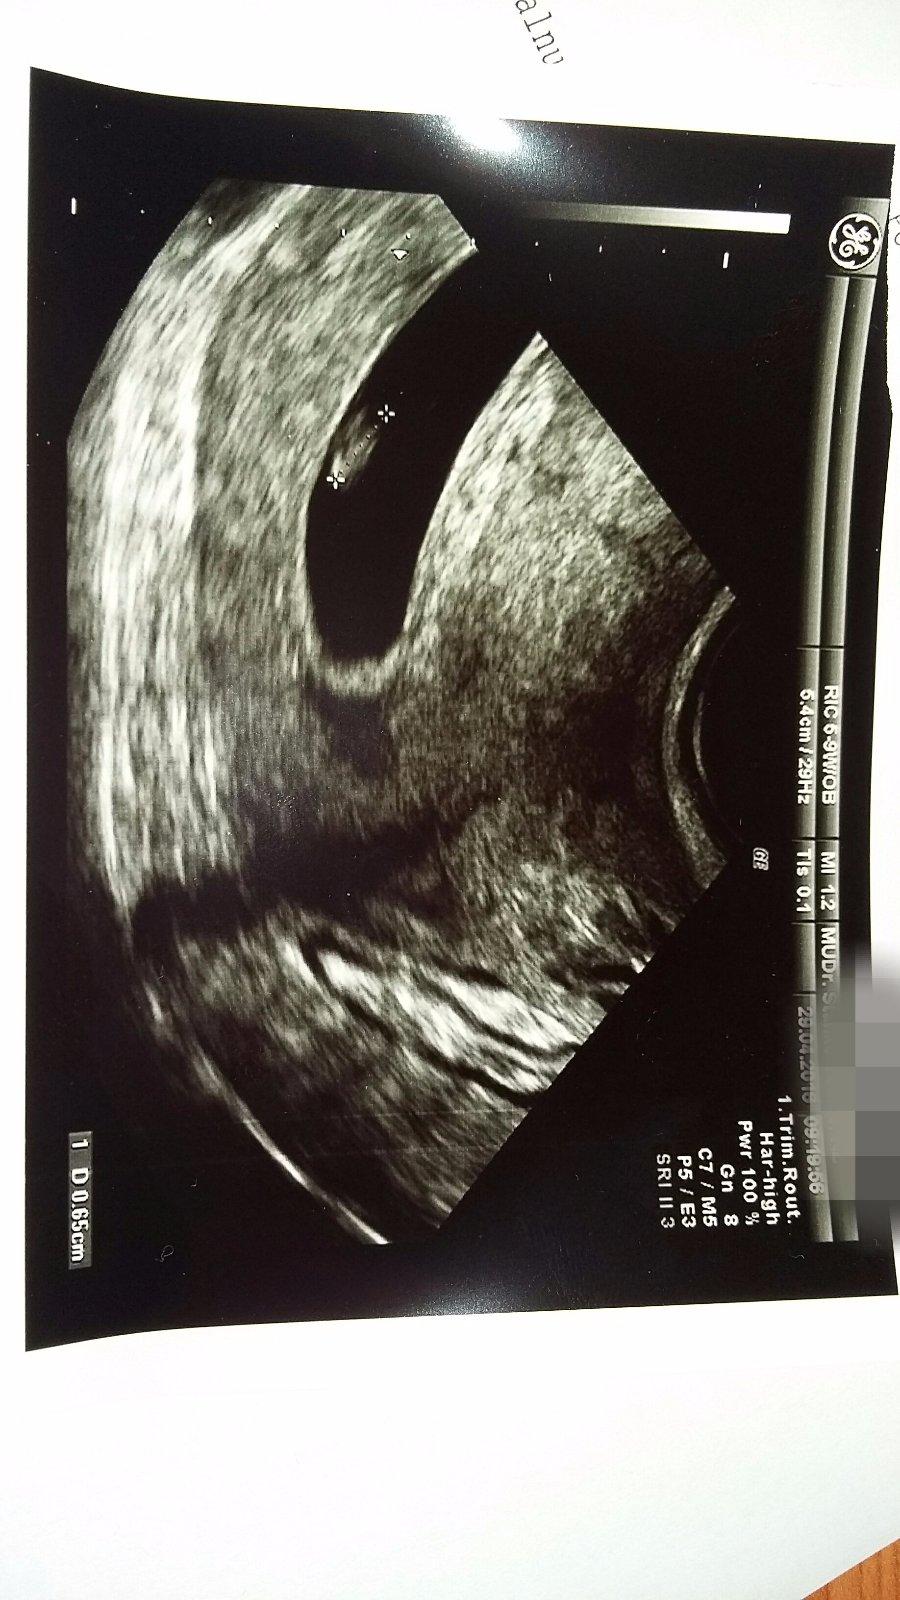

Taak baby, uz mam prvu kontrolu za sebou ☺️ Vsetko je v poriadku, len som dufala ze uz bude vidiet babo. Videli sme zatial len dutinku a zltkovy vak, vraj normalny nalez. Idem zas o tyzden, snad uz bude daco vidiet .

@sugarfree999 tu snimku ti sam urobil lekar alebo si musis o to poziadat sama mna sa nepytala a aj som nato zabudla mala som v hlave to krasne co som videla a teraz mi je aj luto ze nemam fotto ☹

@19871987 Mne dala tie snímky bez toho, aby som si ich pýtala. Dala mi snímku aj minule, keď tam bolo fakt vidno len čiernu bodku. Ale ja žijem v Nemecku, možno tu to lekári robia automaticky a na Slovensku nie,,, tak neviem.

@19871987 ja som bola v Bratislave a dala mi snimku tiez. Ani som si ju nepytala. Asi to zavisi od lekarky.